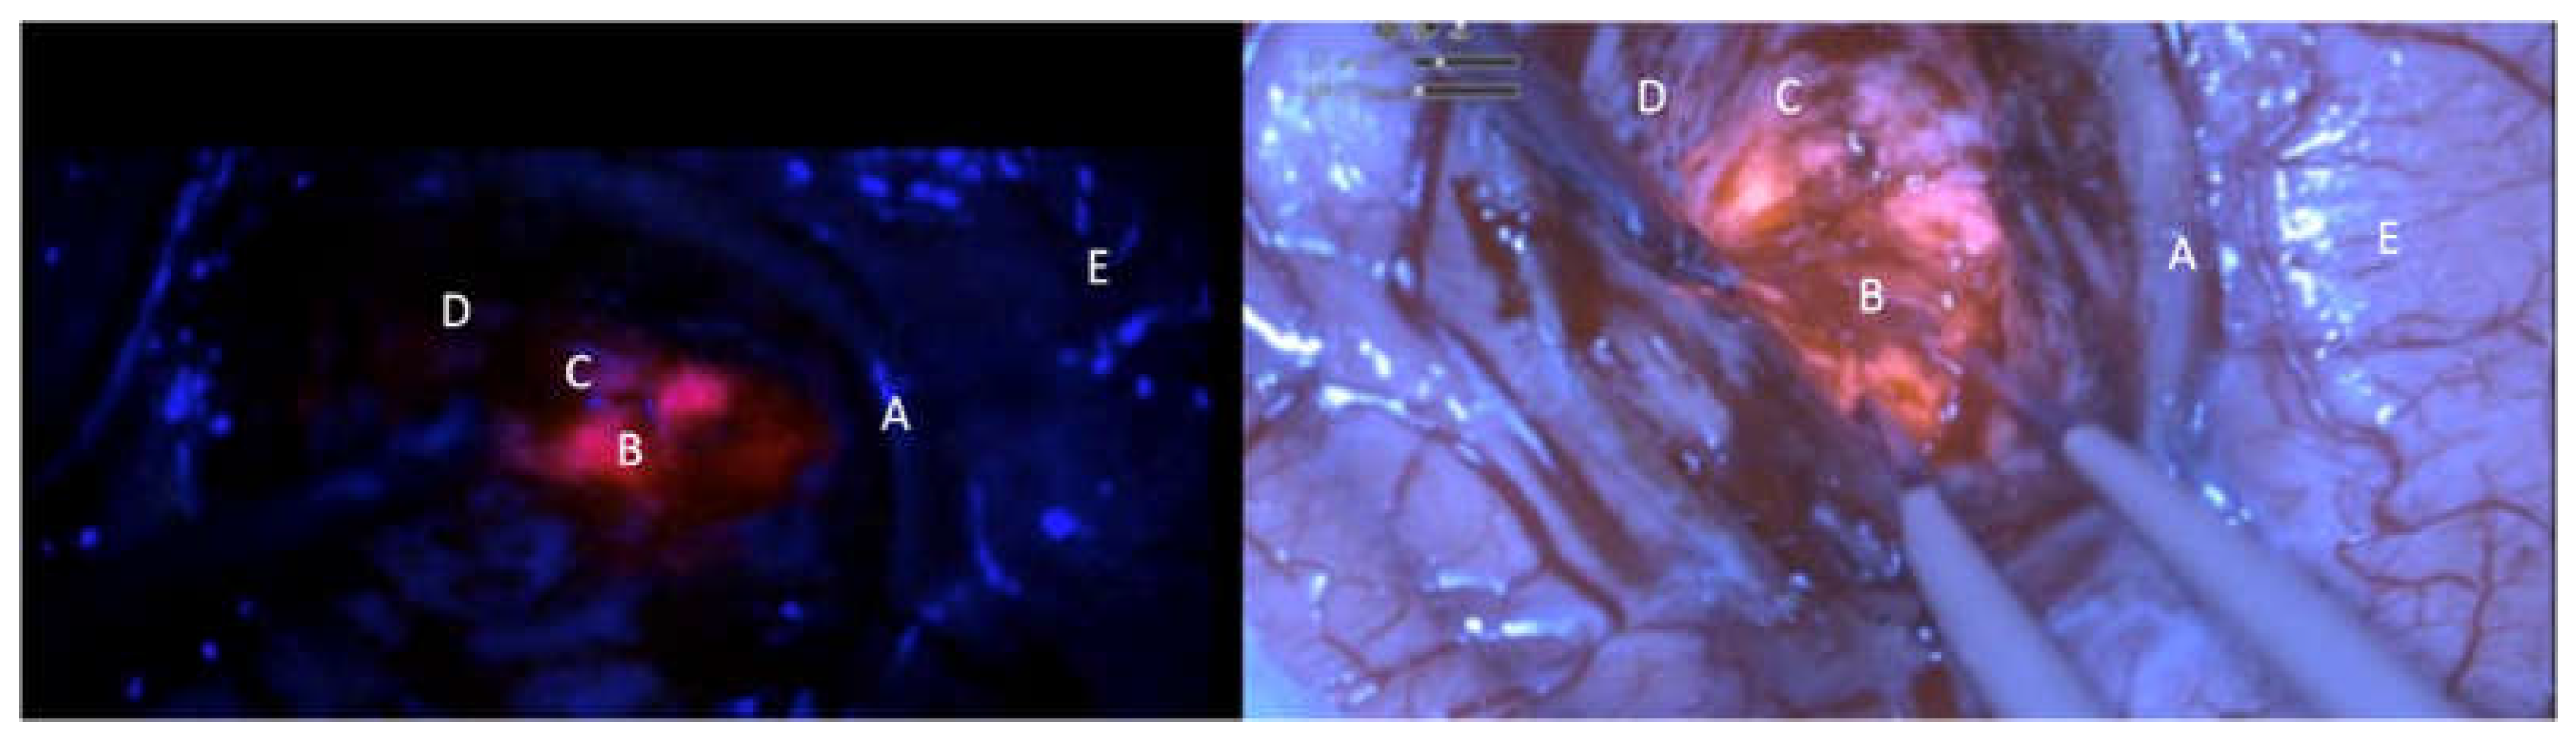

Figure 2. comparative intraoperative pictures of patient N.8; kinevoi900 (left side); Olympus orbeye exoscope (right side). A: vascular structure; B: intense red area (lava-like); C: Faint pink or pinkish area; D: blue area; E: cortical surface.